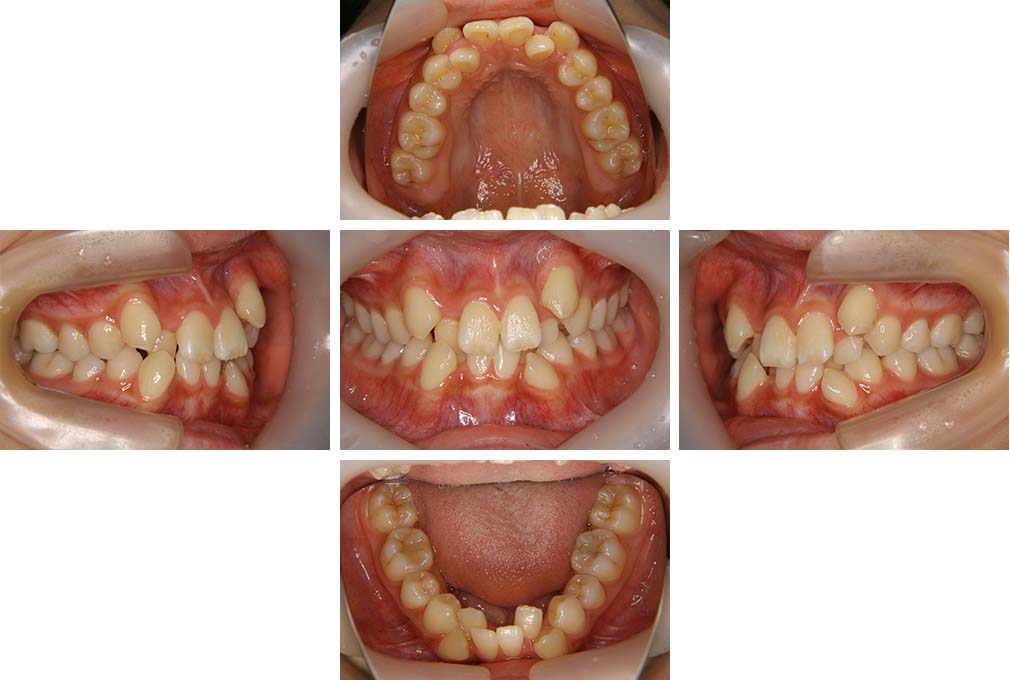

CASE:04

アングルⅢ級傾向を持つ叢生

初診時年齢 22歳

性別 女性

治療費の目安 105万円程度(治療開始時)

上顎右側犬歯が唇側に転位していることを主訴に県内歯科医院から紹介来院された。骨格的にはⅢ級傾向で上顎右側犬歯が唇側転位となり、側切歯が口蓋側に転位していた。下顎前歯が叢生になっていることも相まって上下の正中線は右側に大きくずれていた。アングルⅢ級傾向を持つ上下顎前歯部叢生と診断した。

上下顎小臼歯を抜歯していただき上顎舌側、下顎唇側マルチブラケット装置を使用して動的治療を行った。矯正用ゴムの使用など協力状態も良く、正中線の大きな移動があったのも関わらず2年10カ月で装置を撤去し保定へ移行した。保定移行後14年が経過し、ご息女の診察でご来院いただいていたことから、口腔内を拝見したが、下顎前歯のわずかなずれがあったものの大きな歯列の乱れはなく歯列は安定していた。動的治療期間2年10カ月間。

治療前

22歳6か月

治療後

動的治療期間2年10カ月間

25歳6か月

治療終了

動的治療終了後2年2カ月

28歳8か月

14年経過

動的治療終了後14年7カ月

40歳1か月